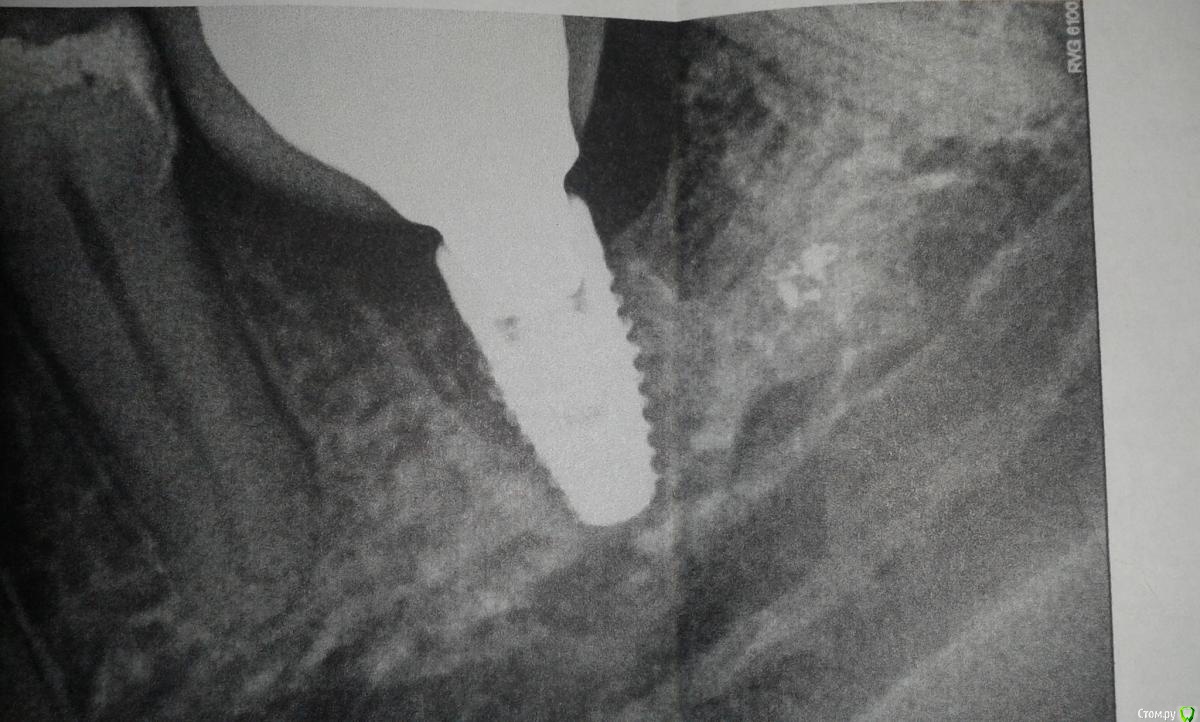

Tina99 Опубликовано 11 октября, 2015 Поделиться Опубликовано 11 октября, 2015 Здравствуйте! Помогите пожалуйста разобраться. В мае этого года установила имплант. В августе сделали на него протезирование. В момент протезирования, ортопед сказал,что мало прикрепленной десны, но в принципе не критично и коронку можно ставить, и нужно будет через два месяца ему показаться для наблюдения за ситуацией. Изначально при чистке зубов, была болезненность десны, поскольку она вся была подвижная и нежная. Примерно неделю назад десна у импланта воспалилась, стала болеть, при надавливании вытекала кровь, через пару дней, вместе с кровью были белые капли с неприятным запахом. Сейчас уже болит не только десна, а боли в челюсти,отдает в ухо,висок и шею,общее самочувствие тоже ухудшилось. Дело в том,что я сейчас в отъезде и своему врачу не могу показаться.В том городе, где я сейчас нахожусь, сделала рентген и сходила к хирургу на консультацию,который сказал, что это периимплантит и часть кости уже рассосалось, назначил антибиотики. Взяла уже билет в свой город, через несколько дней покажусь своему врачу. Хотелось бы услышать ваше мнение, к чему вообще готовиться. Готовлюсь,конечно, к худшему,но надеюсь на лучшее. Ссылка на комментарий

Tina99 Опубликовано 11 октября, 2015 Автор Поделиться Опубликовано 11 октября, 2015 (изменено) Спасибо за ответ. Просто врач, у которого была, именно по снимку и сказал, что кость уже частично рассосалась. И именно после снимка сказал, что это периимплантит. Просто хотела убедиться действительно ли это так, ведь диагноз периимплантит ставят именно после снимка, или это не так? А фотоснимки какие Вы имеете в виду? Фото десны? могу сделать Изменено 11 октября, 2015 пользователем Tina99 Ссылка на комментарий

колесников Опубликовано 11 октября, 2015 Поделиться Опубликовано 11 октября, 2015 Это не периимплантит в прямом смысле. Скорее краевая резорбция. Такое случается. Имплант нобель? Пока применяйте ирригатор (если есть с собой), метрогил-дента,нпвс. Ссылка на комментарий